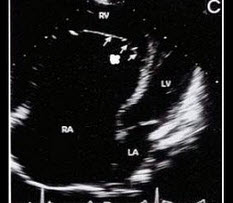

55、单项选择题

孕8周时感冒,产前超声检查胎儿心脏见图,最可能的诊断是()

A.单心室

B.房间隔缺损

C.室间隔缺损

D.大动脉转位

E.正常心脏